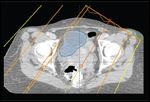

FIGURE 6

IMRT Beam Orientation FIGURE 7

Radiation Fluence Map

Figures 2 through 5 compare a 3D conformal radiation therapy plan (Figures 2 and 4) with an IMRT-based treatment plan (Figures 3 and 5). Figures 6 and 7 illustrate a representative IMRT field with associated dose fluence map. The differences in sagittal radiation dose distribution are shown between a 3D conformal plan (Figure 8) vs IMRT plan (Figure 9). A clinically significant advantage of IMRT includes a reduction in normal (high-dose) tissue irradiation resulting in less acute and chronic radiation-related toxicities, including nontarget bowel, bladder, and genitalia. These can often be significant using conventional radiation techniques, leading to potential treatment breaks with poor outcomes. Additionally, IMRT may permit safe radiation dose escalation in selected clinical situations.